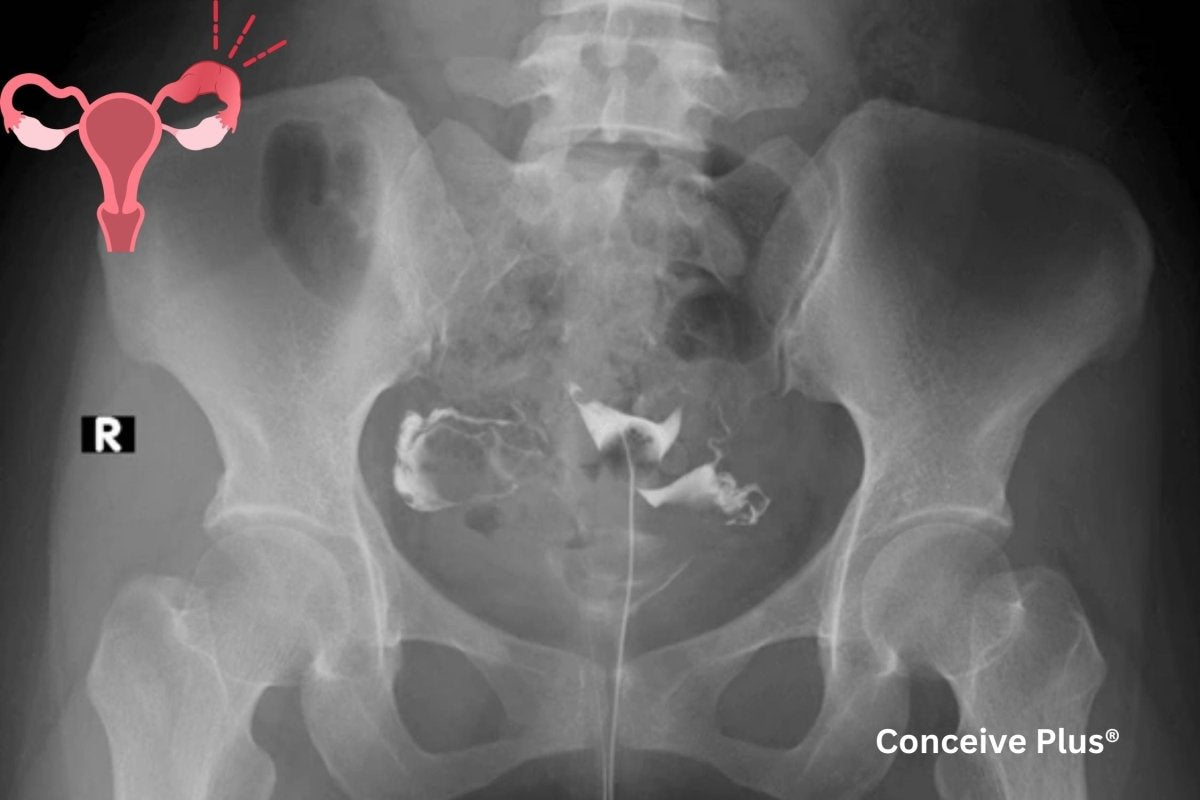

La histerosalpingografía consiste en inyectar un medio de contraste a través del cuello uterino, lo que permite a los profesionales de la salud obtener radiografías del útero y las trompas de Falopio. Al evaluar el recorrido del medio de contraste por el aparato reproductor, los especialistas pueden determinar si existen obstrucciones o problemas estructurales. Esta prueba suele recomendarse a personas con dificultades para concebir o cuando un profesional de la salud sospecha que la forma o el estado del útero y las trompas de Falopio pueden influir en los problemas de fertilidad.

Dado que la HSG ofrece información detallada, a menudo se considera uno de los primeros pasos en las evaluaciones de fertilidad. Si se realiza correctamente, puede proporcionar información crucial sobre fibromas uterinos, pólipos, tejido cicatricial u obstrucción de las trompas de Falopio. Aunque el procedimiento en sí suele durar solo unos minutos, la preparación y el seguimiento pueden prolongar la estancia en un centro de salud [ 1 ] .